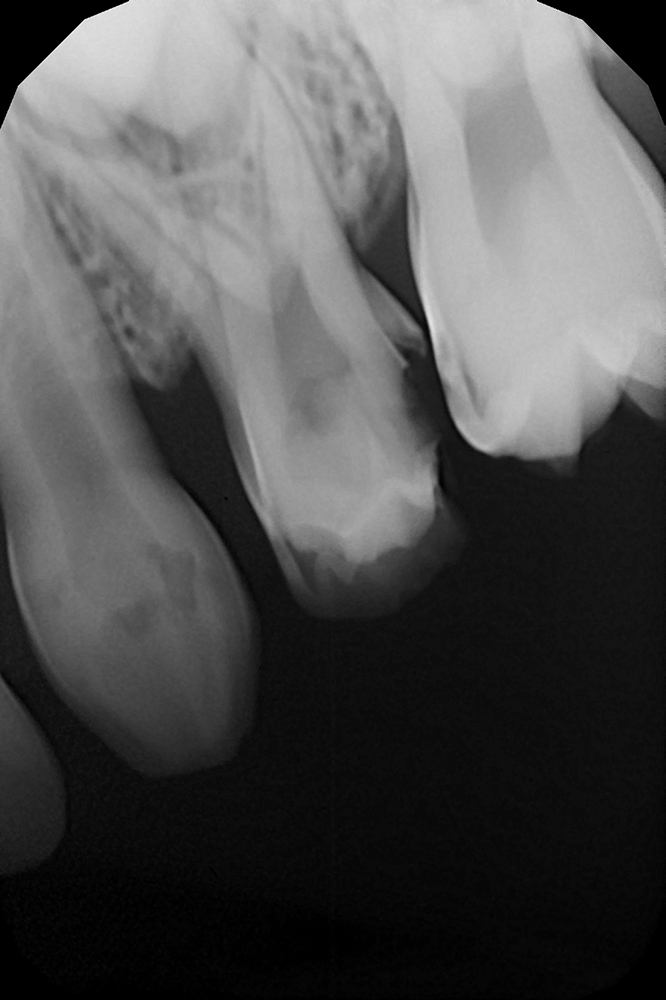

Диагностика и лечение скрытого кариеса на постоянном зубе у семилетнего ребёнка